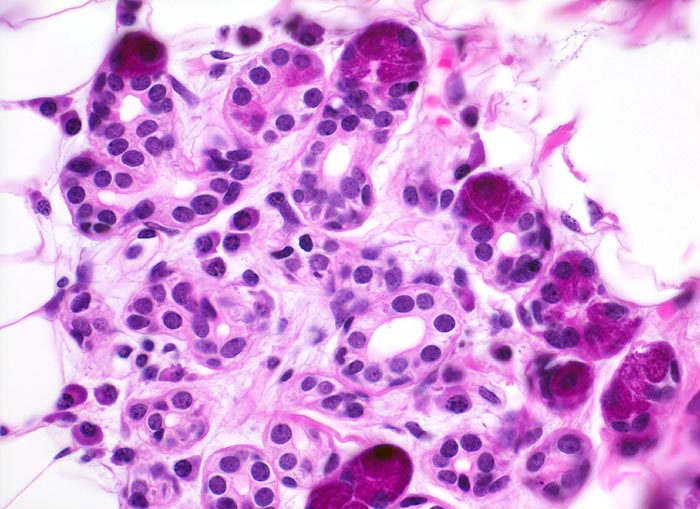

Adenoidzystische Karzinome zeigen drei Wachstumsmuster (in abnehmender Reihenfolge): kribriform, tubulär und solide. Die Hohlräume in den kribriformen Arealen entsprechen keinen echten Drüsenlumina, sondern sind Bestandteil des Tumorstromas. Sie enthalten PAS positives Sekret oder hyaline Substanzen. Die strangförmigen Tubuli begleitet von hyalinem Stroma. Typischerweise (allerdings nicht im vorliegenden Präparat) kann eine Perineuralscheideninvasion nachgewiesen werden. Kleine Tumoren können scharf begrenzt sein, grössere Tumoren wachsen infiltrativ.

• Reste einer rein serösen Speicheldrüse (rechts).

• Unscharf begrenzter, aus kribriformen, tubulären und soliden Zellformationen aufgebauter infiltrativ wachsender Tumor.

• Mikrozystische Hohlräume in den kribriformen Tumorarealen enthalten eosinophiles hyalines Material.

• Tubuli mit zentralem Lumen werden ausgekleidet von einer inneren helleren Epithelschicht und einer äusseren dunkleren Myoepithelschicht.

• Basaloide kleine Tumorzellen mit wenig Zytoplasma.